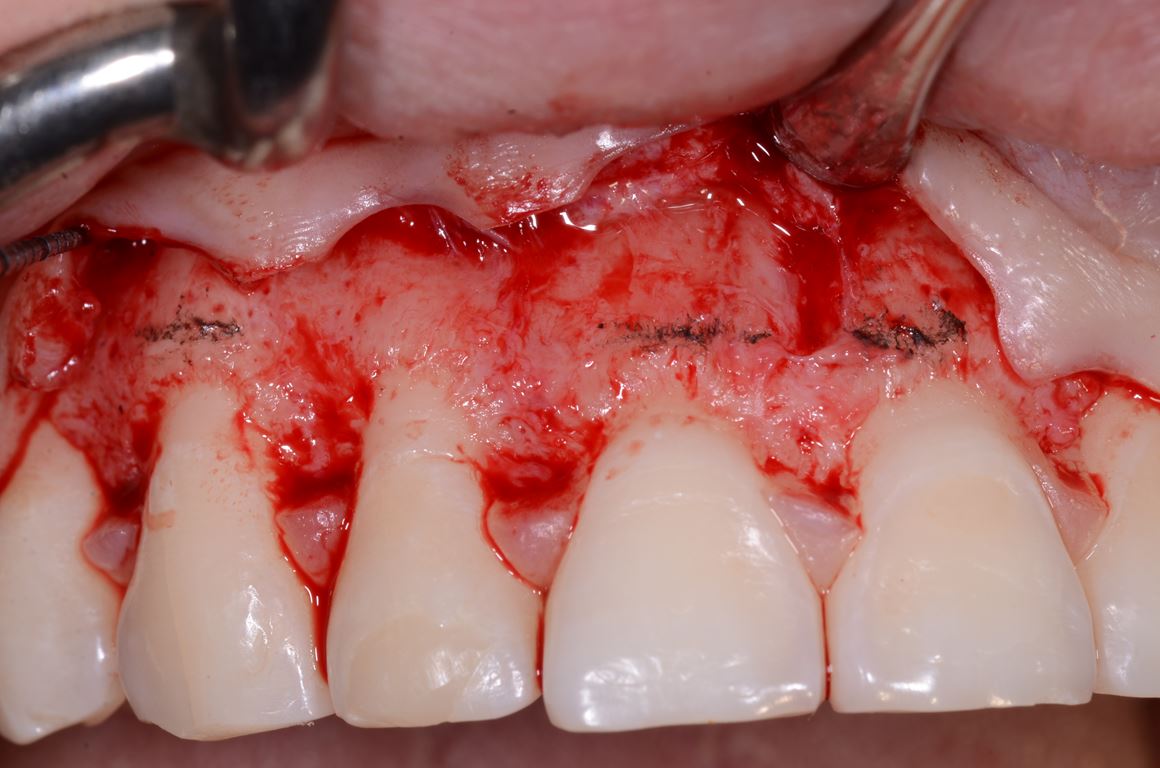

Analiza fotografii z mock-upem potwierdziła konieczność wydłużenia koron klinicznych wszystkich zębów przednich o około 2 mm w kierunku dokoronowym oraz zębów 13-21 w kierunku dowierzchołkowym, w celu zharmonizowania poziomu zenitów dziąsłowych. W związku z tym w okolicy zębów 13-21 wykonano zabieg chirurgicznego wydłużania koron (ryc. 28, 29).